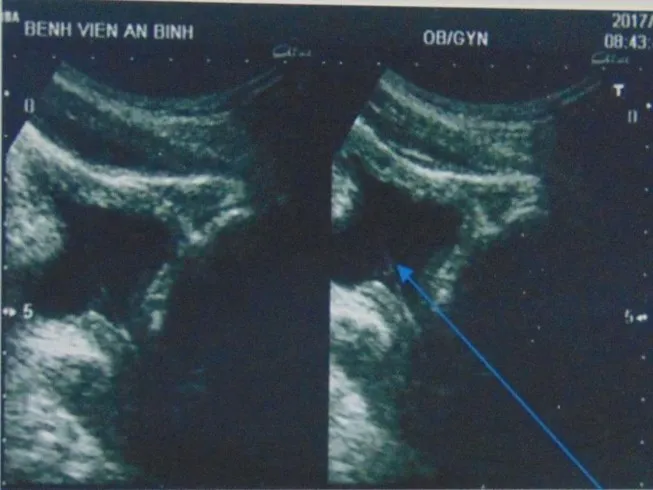

Dị vật bị kẹt trong đường từ niệu đạo tới bàng quang. Ảnh: PLO.VN

Theo lời bệnh nhân, do sờ thấy có một vật thể rắn (nghi sỏi) ở đầu lỗ tiểu nên anh đã tự lấy cọng cỏ đưa vào để khều sỏi ra. Bằng cách này, anh đã lấy được một miếng sỏi nhỏ ra ngoài. Tuy nhiên, viên sỏi lại bị cọng cỏ đẩy sâu vào trong khiến anh bị tiểu khó, tiểu ra máu…

Kết quả siêu âm không phát hiện sỏi ở lỗ tiểu nhưng có một dị vật mỏng dài 2 cm kẹt trong đường từ niệu đạo tới bàng quang, quan sát kỹ đó là một mẩu của cọng cỏ. May mắn cho bệnh nhân là sau đó mẩu cọng cỏ này đã tự được tống ra ngoài khi đi tiểu sau lần khám.